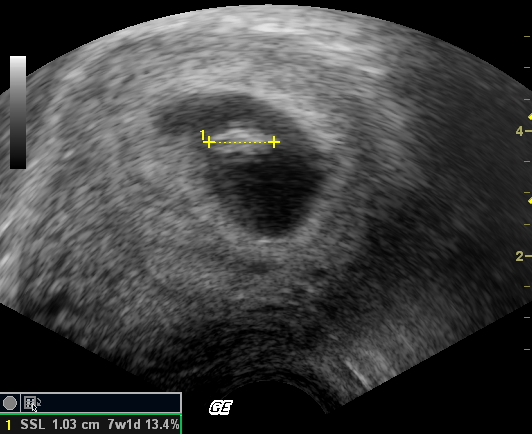

Mam war nun bei ihrem Frauenarzt und der machte per Ultraschall das erste Foto von mir:

Ich stellte fest, dass ich viel zu klein bin und schnell wachsen muss, um besser auf den nächsten Bildern erkannt zu werden.

Dann war wieder Fototermin:

Jetzt hat Mam so einen Mutterpass. Da stehen lauter komische Daten und Eintragungen über mich drin. Leider hat niemand meiner Mami erklärt, was die denn zu bedeuten haben. Zum Glück gibt es ja Papa und das Internet...

Demnach sind wir jetzt in der 12ten Schwangerschaftswoche und ich bin 4,81 cm gross. Man bin ich gewachsen. Mam hör ich immer reden, dass sie sich gar nicht vorstellen kann, dass ich jetzt schon fast 5 cm gross in ihr bin. Wenn die wüsste, dass ich mich noch viel breiter bei ihr machen werde...

Was Mami auch sehr beruhigt ist die Tatsache, das ich allein in ihrem Bauch bin, nix da mit Zwillingen oder dergleichen... Jedenfalls hab ich noch niemand weiter hier im Bauch entdeckt und die Ärztin hat ja auch ziemlich genau geschaut...

Die Ärztin hat nun auch einen Geburtstermin errechnet, demnach müsste ich am 17-06-2008 Mamas Bauch verlassen. Mal sehen... |